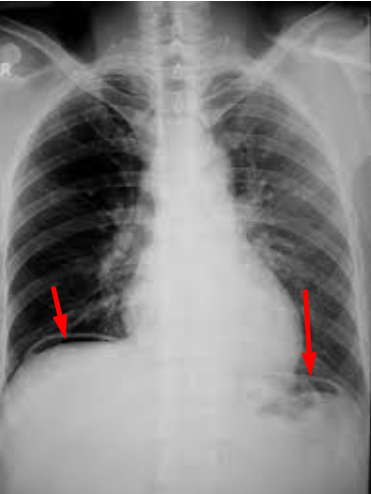

Sau khi được làm những xét nghiệm cần thiết, bệnh nhân Đ được chẩn đoán: Viêm phúc mạc do thủng ổ loét hành tá tràng. Ngay sau đó, bệnh nhân Đ được các bác sĩ mổ cấp cứu phẫu thuật nội soi khâu lỗ thủng ổ loét hành tá tràng, lau rửa, dẫn lưu ổ bụng.

![]() |

| Hình khí tự do dưới cơ hoành (mũi tên đỏ) trước mổ của bệnh nhân Đ, chứng tỏ có thủng tạng rỗng |